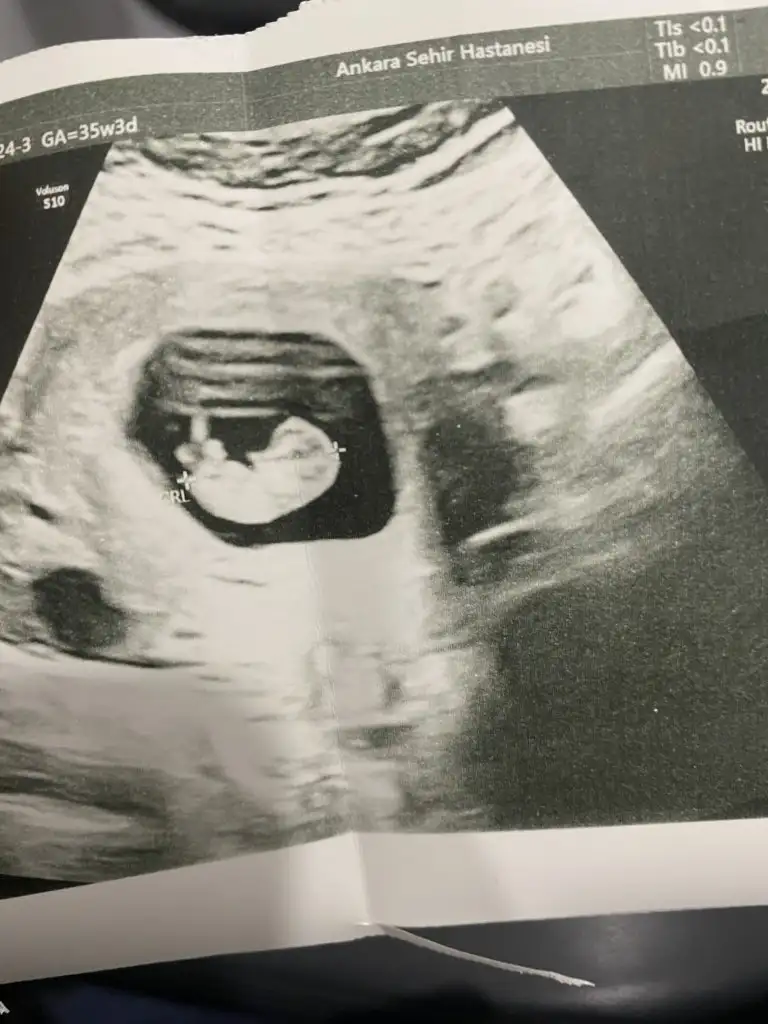

Arkadaşlar Buda benim 14 haftalık ultrason görüntüm sizce cinsiyet ne olabilir tahmin yapabilir misiniz şimdiden çok teşekkür ederim

Benim bebeğimede yorum yaparmısınız 12 haftalıkBen nuruna gore anlıyorum kızınız olucak inşallah

Nubu duz kızBenim bebeğimede yorum yaparmısınız 12 haftalık